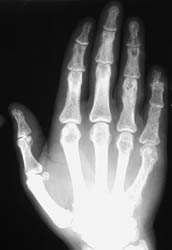

The hands are the most common site of osseous involvement. The middle and distal phalanges and less frequently the proximal phalanges and metatacarpals may show changes associated with sarcoidosis. Involvement at the wrist occurs much less frequently.

An abnormal trabecular lace-like pattern of destruction can often be seen at the phalanges and metacarpals of the hands. Cystic changes and osseous destructive lesions may also be evident. Acro-osteosclerosis with the radiographic appearance of terminal phlangeal sclerosis is not specific; however, it has been reported in up to half of the patients with skeletal abnormalities of sarcoidosis. Soft tissue swelling, and inflammatory skin nodules (erythema nodosum) are occasionally noted. If the wrist is involved, cystic changes and lytic lesions may be present.

The abnormal trabecular pattern of destruction at the hands is fairly characteristic of sarcoidosis. If osseous destruction is present at the distal phalanges, the appearance may be similar to findings associated with scleroderma. However, scleroderma has fairly characteristic associated soft tissue findings which distinguish it from sarcoidosis.